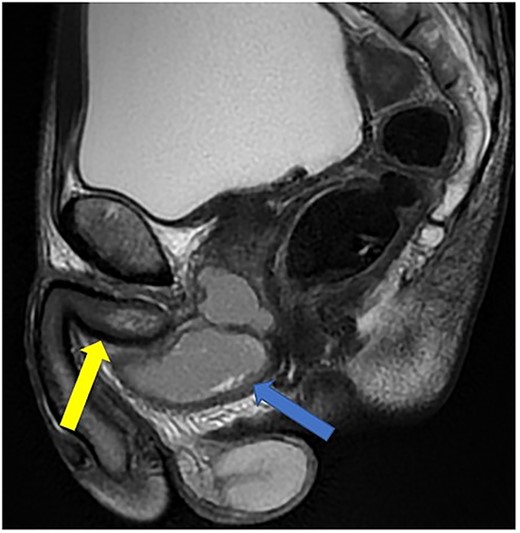

Imaging was suggestive of an infected Cowper’s syringocele. As the patient was clinically stable, a trial of antibiotic therapy was suggested. Repeat MRI a week later showed that the collection had extended into the corpus spongiosum, which now appeared expanded with the fluid density signal (Fig. 1). On a review, the urethral catheter was thought to be impairing potential drainage of the collection. It was removed, and a suprapubic catheter was inserted. Ultrasound guided aspiration failed to drain a significant amount of pus, which also grew S. anginosus. There was also radiological suspicion of a colovesical fistula. The patient was reviewed by the colorectal surgeons, who felt that as there were no other symptoms relating to the fistula, and the patient was physiologically frail, and defunctioning of the bowel would be inappropriate. Likewise, the patient was deemed too frail for any surgical management of the collection. He was discharged after a total of 6 weeks’ antibiotics. Repeat MRI 4 months later (Fig. 2) showed a smaller but persistent collection.

Case 1: T2-weighted axial image 4 months later, showing slight reduction in the size of the collection (arrow).

In view of his significant comorbidities and the absence of any clinical signs or symptoms, he is being managed conservatively with a long-term suprapubic catheter.